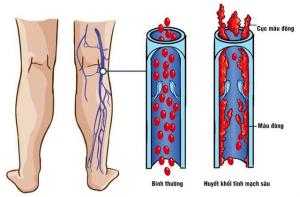

Thrombolex announces 510(k) clearance of Bashir catheter systems for thromboembolic disorders